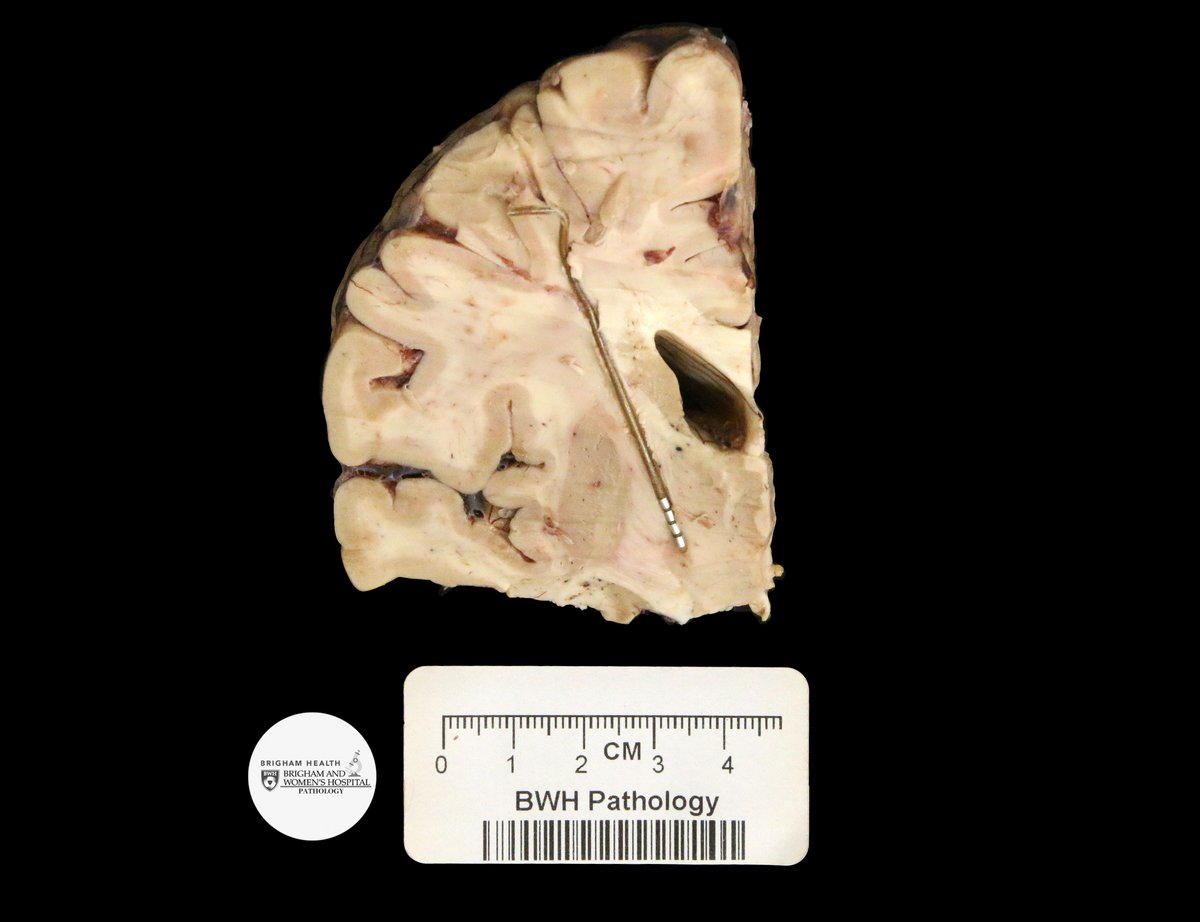

A teaching point from our Editors. How do you distinguish between intrapancreatic bile duct carcinoma and pancreatic ductal carcinoma? Samuel Freire